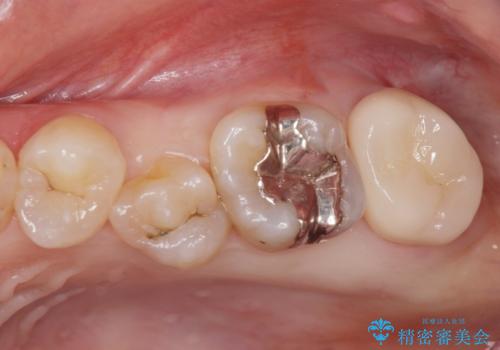

[ 歯肉縁下齲蝕 ] 歯周外科を行った虫歯治療

黒くなった奥歯をジルコニアクラウンに